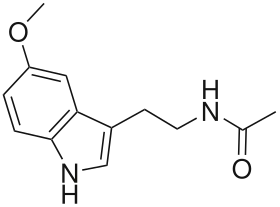

| Melatonin | Animals, plants, microbes | 5-OCH3 | H | O=C-CH3 | 5-methoxy-N-acetyltryptamine | 73-31-4 |